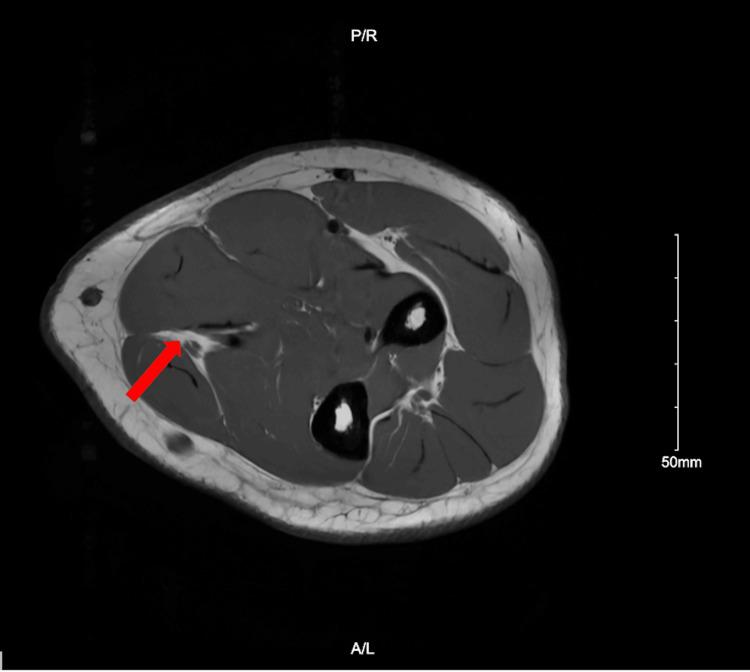

While peripheral nerve schwannomas have a relatively low incidence, schwannomatosis, the condition in which one forms multiple recurring schwannomas, is an even rarer phenomenon and can be hard to detect given its ability to mimic other conditions. We report a case of a 35-year-old male who presented with a mass in his left wrist and forearm, volar pain in his forearm, and numbness in his fingers. Magnetic resonance imaging (MRI) revealed a bilobed heterogeneous neural sheath tumor in the distal left ulnar nerve. The tumor was resected including extensive internal neurolysis using a Zeiss operative microscope. Post-operative biopsy confirmed an encapsulated schwannoma. The patient did well initially but developed worsening pain in his forearm and weakness. He had persistent paresthesias in the ulnar nerve distribution. He underwent a repeat MRI almost one year later, which showed thickening of the ulnar nerve proximal to the area of resection with an 8.5 mm hyperintense nodule. The patient underwent a subsequent resection with extensive neurolysis, which confirmed that the mass was a benign non-invasive schwannoma. At six weeks post-surgery, the patient's forearm pain was significantly improved and his range of motion returned to baseline. Our case demonstrates the importance of post-operative follow-up in schwannomas with appropriate imaging if symptoms persist or recur.

虽然周围神经鞘瘤的发病率相对较低,但神经鞘瘤病(即形成多个复发性神经鞘瘤的病症)是一种更为罕见的现象,并且鉴于其能够模仿其他病症,可能难以检测。我们报告一例35岁男性病例,该患者表现为左手腕和前臂有肿块、前臂掌侧疼痛以及手指麻木。磁共振成像(MRI)显示左尺神经远端有一个分叶状的异质性神经鞘瘤。使用蔡司手术显微镜切除肿瘤,包括广泛的内部神经松解术。术后活检证实为包膜性神经鞘瘤。患者最初情况良好,但前臂疼痛加重且出现无力。他在尺神经分布区域持续存在感觉异常。近一年后他接受了重复MRI检查,结果显示切除区域近端的尺神经增粗,有一个8.5毫米的高信号结节。患者随后接受了再次切除及广泛的神经松解术,证实该肿块为良性非侵袭性神经鞘瘤。术后六周时,患者的前臂疼痛明显改善,活动范围恢复到基线水平。我们的病例表明,对于神经鞘瘤,如果症状持续或复发,进行适当影像学检查的术后随访非常重要。